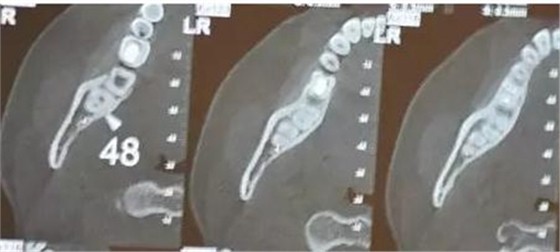

患者、女、24歲,主訴:右側(cè)下后牙自發(fā)疼數(shù)月。專(zhuān)科檢查:48垂直位、萌出約1/2,合面齲壞,探痛明顯,全景片檢查;48牙根與下頜管重疊,加拍CBCT檢查:下頜管位于48根尖下方的舌側(cè),牙根并未進(jìn)入下頜管內(nèi)。診斷:48中位垂直阻生伴牙髓炎。治療計(jì)劃:建議拔除48.患者同意治療方案,簽術(shù)前知情同意書(shū)。

圖4.CBCT的水平斷面檢查:48牙根不在下頜管內(nèi),但與下頜管緊鄰